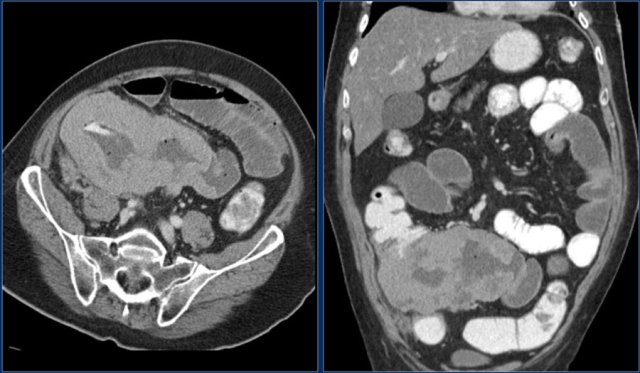

The images show a circumferential mass with shouldering of the margins.

Large adenocarcinomas can mimic a lymphoma as in this case.

The images show an irregular mass in the proximal jejunum.

Although it is a large circumferential growing mass, the lumen is not obstructed.

There is a large conglomerate of hypodense lymph nodes in the adjacent mesentery, consistent with necrotic lumph node metastases (lower image).

This proved to be an adenocarcinoma, but these findings could very well represent a lymphoma.

Here the endoscopic image of the tumor.